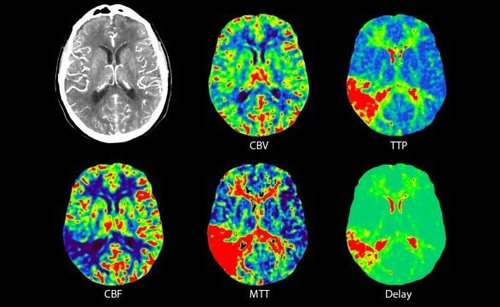

Die Stroke-Evaluation-Plattform von Canon Medical erlaubt die Durchführung einer Perfusionsbildgebung des gesamten Gehirns und eine digitale 4D-Subtraktionsangiographie des intrakraniellen Kreislaufs in nur einer Minute. Mit der Unterstützung durch die 4D-Software wird die Bewertung von Fluss- und Perfusionsfehlern in weniger als fünf Minuten ermöglicht.